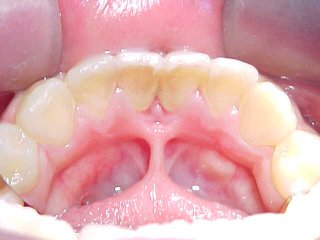

| Esta técnica cirúrgica destina-se à liberação dos movimentos funcionais da língua . Neste caso a inserção mais anterior se mostra aderida à gengiva: